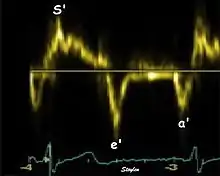

Annular velocities summarize the longitudinal contraction of the ventricle during systole, and elongation during diastole. Peak velocities are commonly used.

Systolic function

Peak systolic annular velocity (S') of the left ventricle is as close to a contractility measure as you can get by imaging[4] (bearing in mind that any imaging method only measures the result of fibre shortening, without measuring myocyte tension). S' has become a reliable measure of global function[5][6][7][8] It shares the advantage of annular displacement, that it is reduced also in hypertrophic hearts with small ventricles and normal ejection fraction (HFNEF), which is often seen in Hypertensive heart disease, Hypertrophic cardiomyopathy and Aortic stenosis.[9]

Diastolic function

As the ventricle relaxes, the annulus moves towards the base of the heart, signifying the volume expansion of the ventricle. The peak mitral annular velocity during early filling, e' is a measure of left ventricular diastolic function, and has been shown to be relatively independent of left ventricular filling pressure.[12][13][14][15] If there is impaired relaxation (Diastolic dysfunction), the e' velocity decreases. After the early relaxation, the ventricular myocardium is passive, the late velocity peak a' is a function of atrial contraction. The ratio between e' and a' is also a measure of diastolic function, in addition to the absolute values.